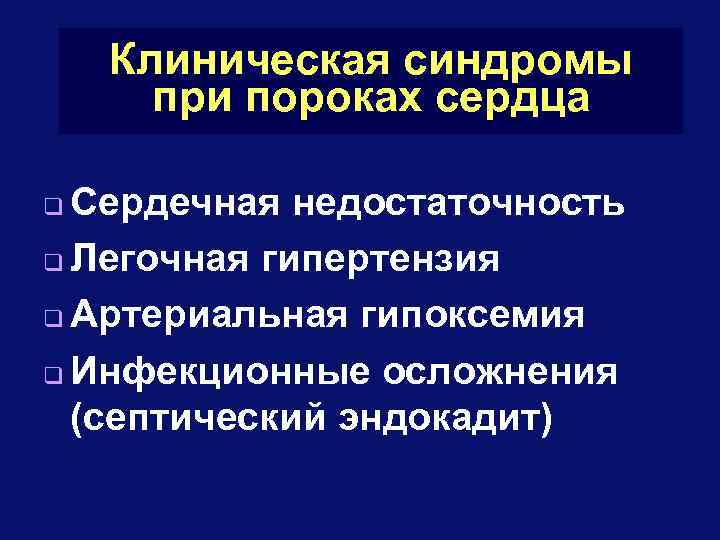

Клиническая синдромы при пороках сердца Сердечная недостаточность q Легочная гипертензия q Артериальная гипоксемия q Инфекционные осложнения (септический эндокадит) q